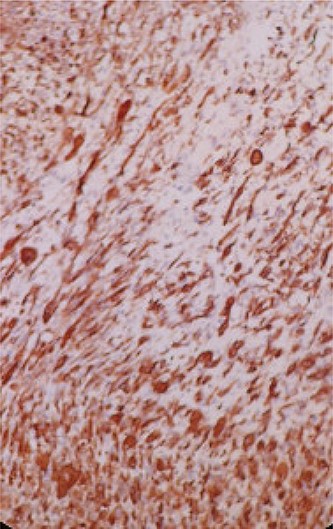

Microscopic overview of the malignant urothelial tumor with sarcomatoid and rhabdomyoblastic components (hematoxylin and eosin * 20).

Immunohistochemical (IHC) study shows the positivity of rhabdomyoblastic cells to the anti-desmin antibody (IHC * 20).